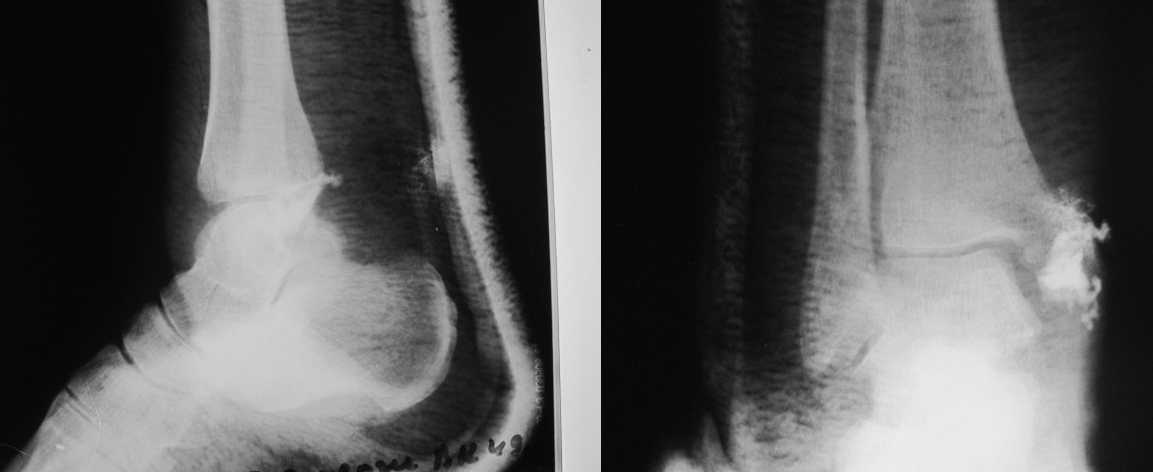

Re: Остеомиелит медиальной лодыжки

Уважаемые коллеги! Прошу прощения за собственную невнимательность. У больной травма не 1 января 2011г., а 1 декабря 2010г., т.е. уже 2 месяца.

Прилагаю данные фистулогрфии. Основной вопрос, все же, лечить консервативно или оперативно? Если оперативно, то какой объем? А что если прийдеться резецировать всю медиальную лодыжку!?